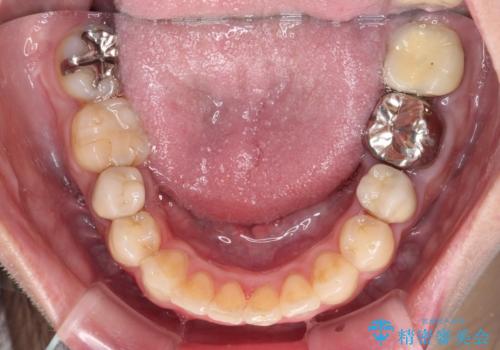

- 他院で抜歯矯正を終えた後、銀色の目立つ奥歯を白くしたいとのことで来院された患者様です。

既にセラミッククラウンが装着されている歯もありますが、不自然な色合いや黒い縁も気になるので、一斉に補綴治療をして統一感を持たせることとしました。

矯正治療を終えたばかりなので、仮歯やセラミッククラウンに置き換えている間に保定がうまくいかなくなる可能性があるため、下顎前歯の舌側を事前にワイヤーで保定しておくこととしました。